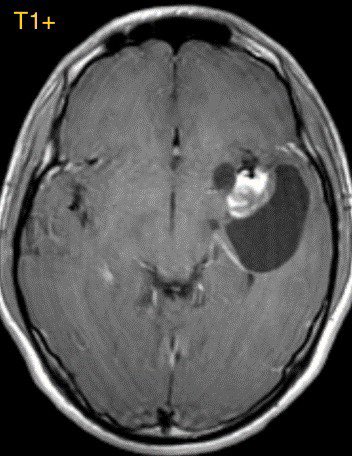

2️⃣ABSCESS

Trapped purulent material leads to LIGHT BULB BRIGHT restriction

DWI is excellent for differentiating tumor from pyogenic abscess as the abscess will have CENTRAL restriction

Abscess should also have vasogenic EDEMA, ENHANCEMENT, and possible dual rim sign (T2 & SWI) ImageImage